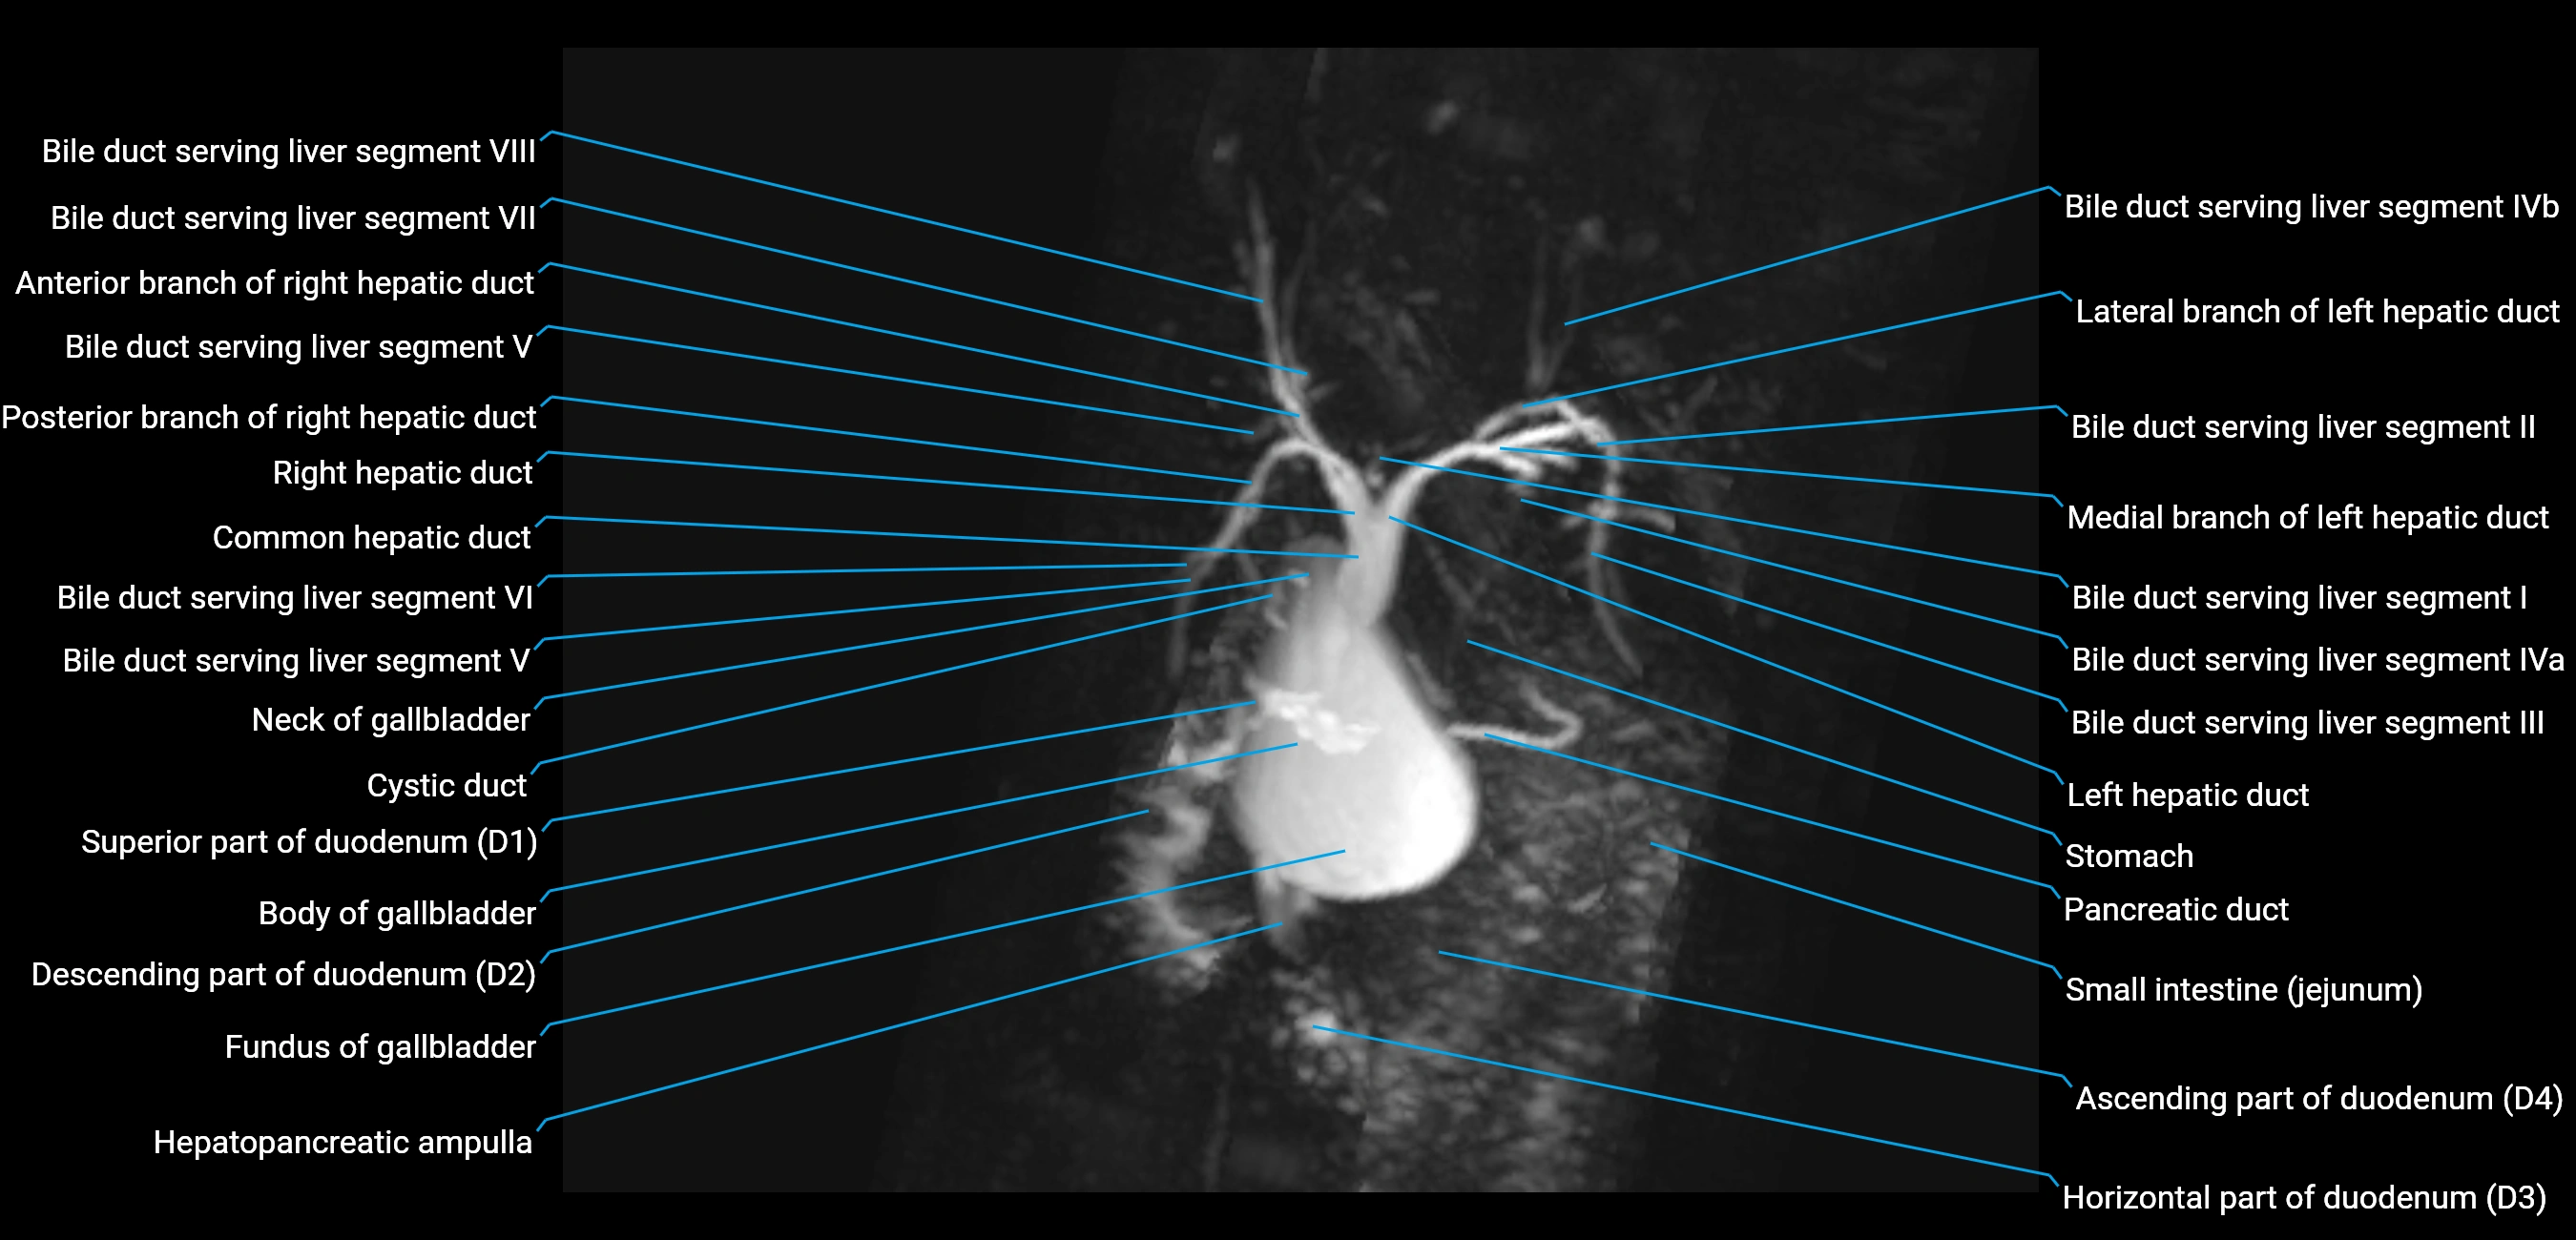

MRI image

image